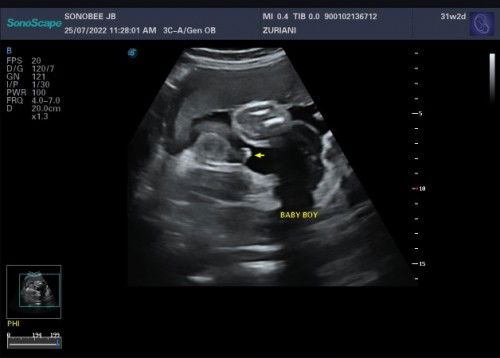

Scan Jantina Baby

Hai mommies sekalian.. Hari tu ada scan jantina baby. Masa ni dah 31 weeks. Katanya baby boy. Rasanya sahih tak? Saya dah lama nakkan baby boy sebab sebelum ni saya dapat baby girl 2 orang dah. Yang ketiga ni harap2 keluarla boy. Sebelum ni scan dua2 baby 1st and 2nd kepit2 tak nampak sampai la keluar baru tahu jantina. Yang ketiga ni alhamdulillah nampak tapi saya tak nak terlampau berharap sangat. Ikut pengalaman mommies yang ada baby boy, pernah scan, betul ke berita ni?